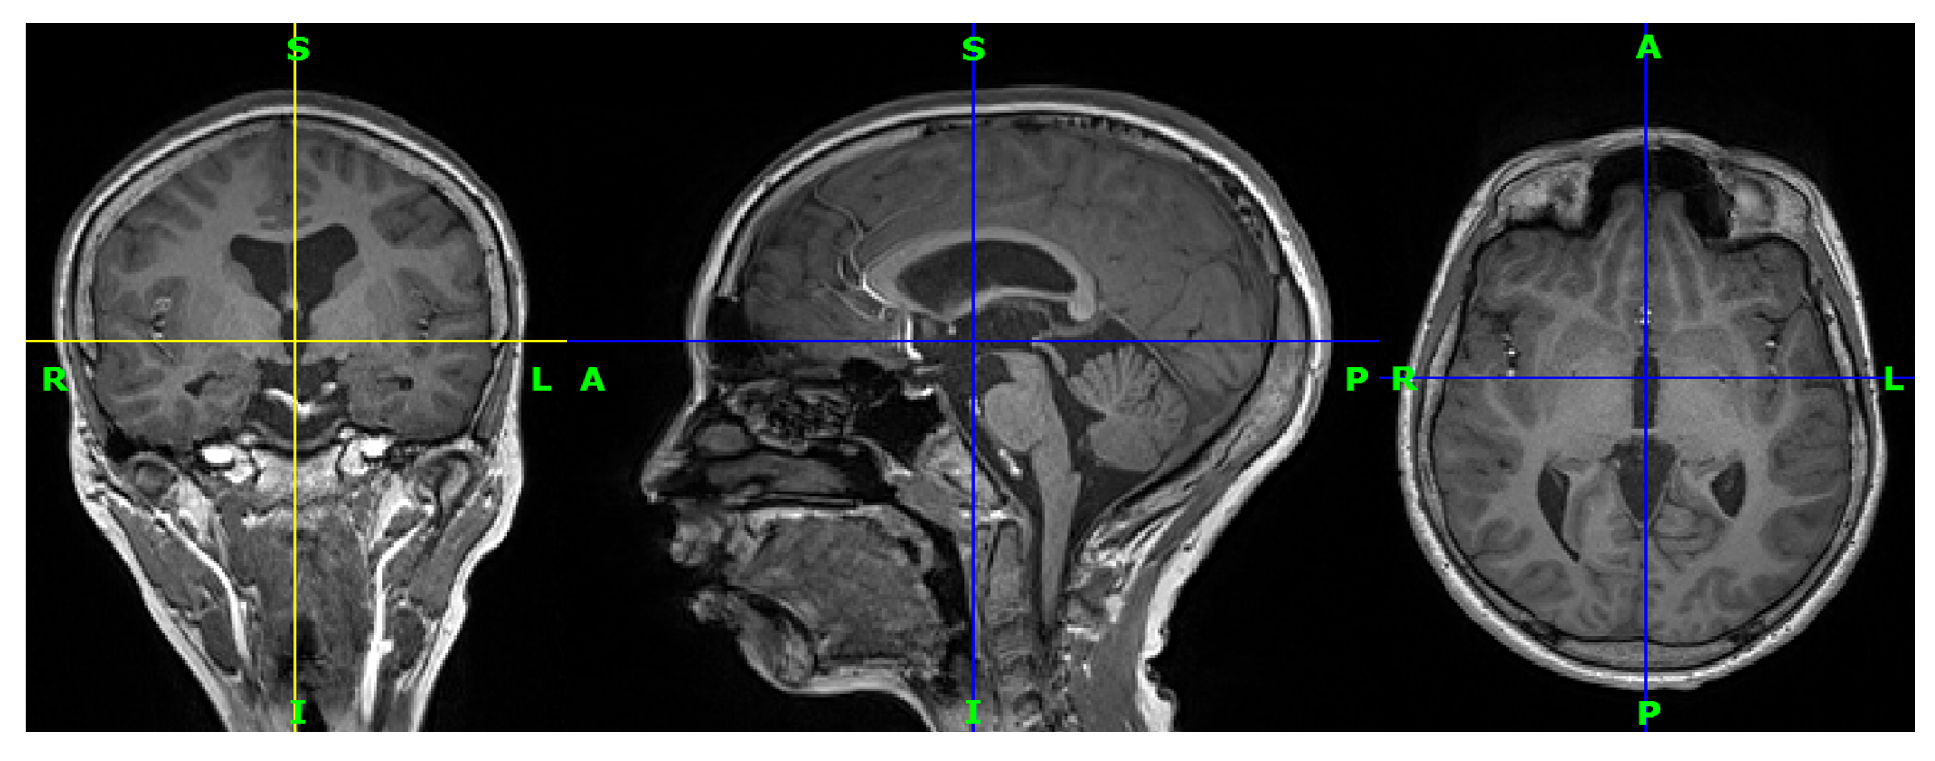

Eleven participants with drug-resistant epilepsy from the epilepsy unit at King Abdul-Aziz University Hospital were included in this study. In addition, eighteen healthy control subjects from the same hospital were included. The subjects are between 22 and 30 years old. Most of them are Saudi. A total of twenty-nine three-dimensional (3D) T1-weighted MRI images were provided, one for each subject. All images are in nifti format (.nii). Figure 5 shows an image from the collected data for the first patient.

Figure 5.

Three-dimensional T1-weighted MRI for a patient from the data set in coronal view, sagittal view, and axial view, respectively. R indicates the right of the brain, L indicates the left of the brain, S (superior) indicates the top of the body, and I (inferior) indicates the bottom of the body.